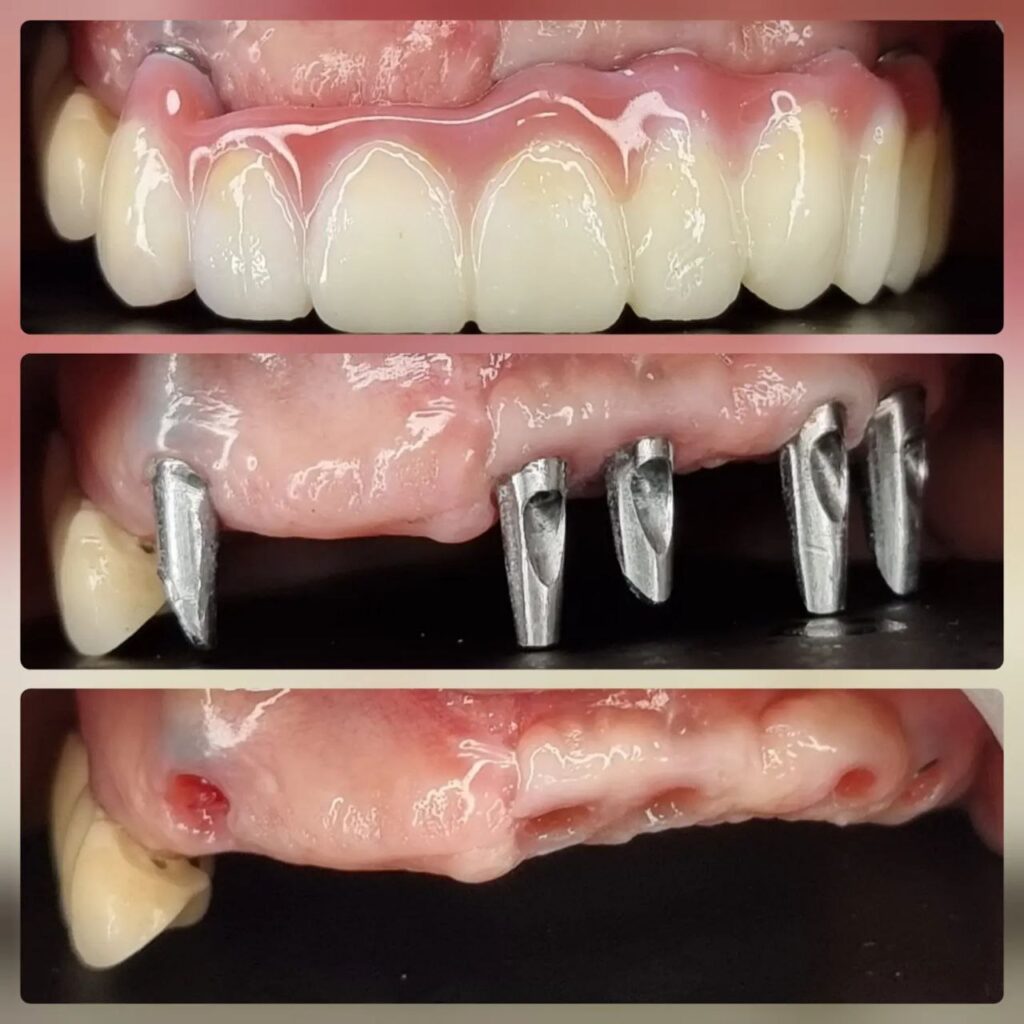

کاشت ایمپلنت دندان

اطمینان حاصل کردن از اینکه دندانهایتان به نحوی زیبا و طبیعی جایگزین شدهاند، از اهمیت بسیاری برخوردار است. ایمپلنت دندان به عنوان یک روش درمانی دائمی در دندانپزشکی شناخته میشود که حاصل آن، یک دندان زیبا و طبیعی در دهان شما خواهد بود.

هرچند که این روش درمانی هزینهی بیشتری نسبت به روشهای دیگر دارد، اما ارزش زیبایی که ایجاد میکند، قابل انکار نیست. ایمپلنتها به قدری شبیه به دندانهای طبیعی هستند که به سختی میتوان آنها را از دیگر دندانها تشخیص داد.